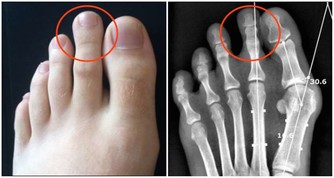

3、肝掌:

與常人的手掌顏色大不相同,普通人的手掌顏色紅潤,而患有肝病的病人手掌心泛白無血色。